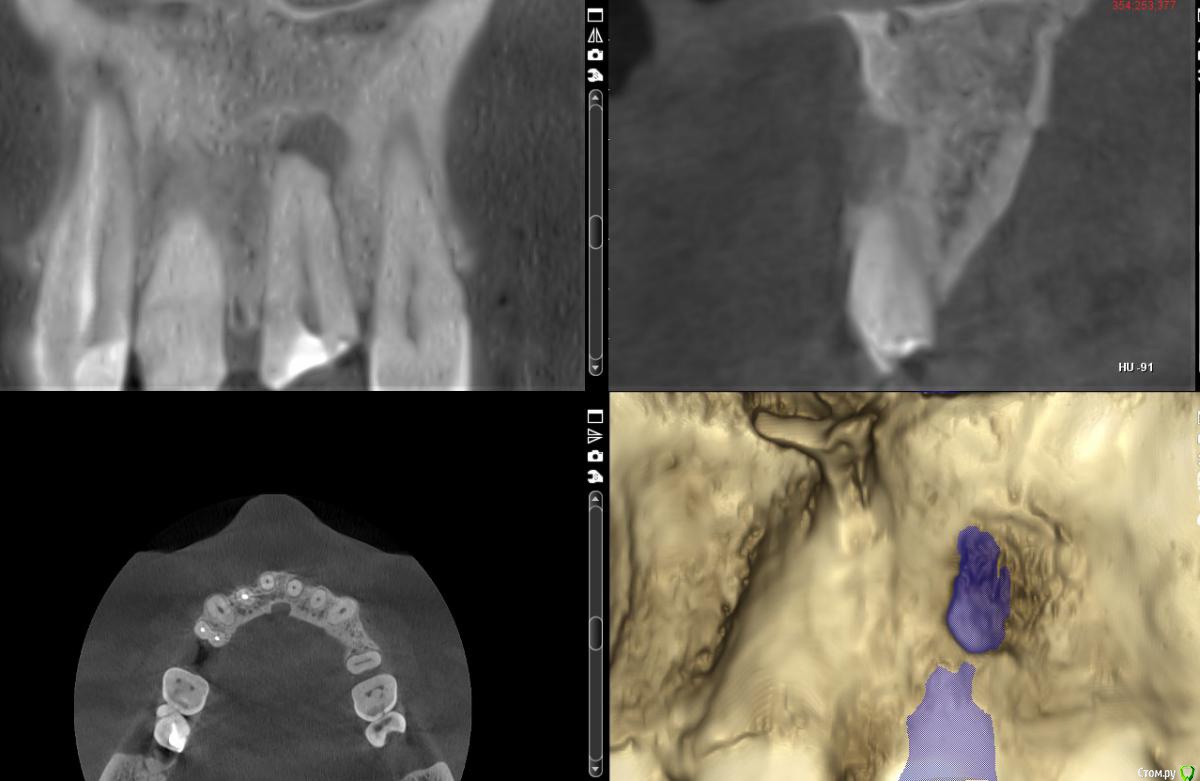

darkdiablo40 Опубликовано 8 августа, 2020 Поделиться Опубликовано 8 августа, 2020 (изменено) Здравствуйте! Поступил пациент на одномоментную имплантацию и удаление 2.1. Хотел бы обсудить с Вами случай. Что смущает: 1) Гранулема с резорбцией вестибулярной стенки в области верхушки. 2) Наличие выраженного широкого резцового канала, т.е. нельзя уйти небно. 3) Тонкая вестибулярная пластинка, нужно подумать, как лучше удалить, думается, что если удалять по классике, то рычагом вестибулярка уйдет.Сам склоняюсь к отсроченной имплантации.Предварительно мои мысли: 1) Выбрать ось имплантации соосно зубу, на несколько градусов более палатинально 2) Отслоиться достаточно хорошо, выполнить кюретаж гранулемы, осмотреть дефект 3) Установить имплантат, зазор заполнить графтом, образовавшееся окно закрыть резорбируемой мембраной.Что вы думаете об этом? Изменено 8 августа, 2020 пользователем darkdiablo40 Ссылка на комментарий

Irouil Опубликовано 8 августа, 2020 Поделиться Опубликовано 8 августа, 2020 (изменено) Нормальные условия для одномоментной имплантации. Даже без idr нормальные, но лучше с ней. А какие окна Вы собираетесь закрывать, если планируете отсроченно крутить? P.S. Лучше создайте свою тему Изменено 8 августа, 2020 пользователем Irouil Ссылка на комментарий

darkdiablo40 Опубликовано 8 августа, 2020 Поделиться Опубликовано 8 августа, 2020 (изменено) Собираюсь одномоментно, но смущают вышеперечисленные особенности, чтобы не привело к дефекту вестибулярной пластинки в области имплантата.Закрывать писал при одномоментной методике. Изменено 8 августа, 2020 пользователем darkdiablo40 Ссылка на комментарий